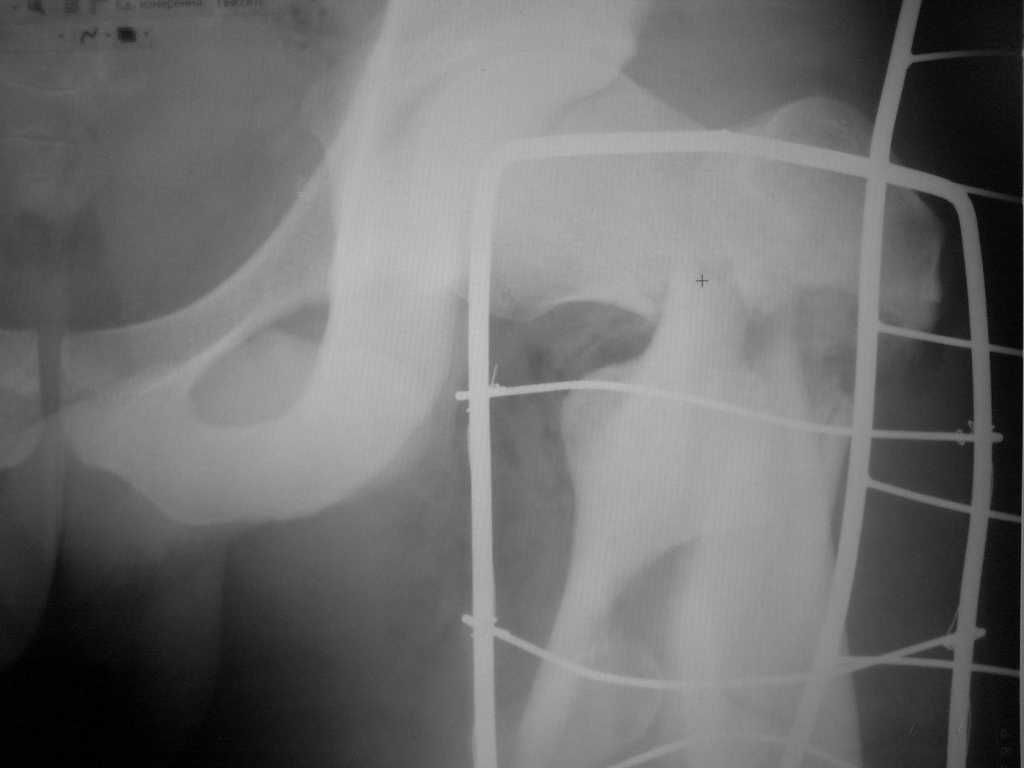

[Ortho] оскольчатый чрезвертельный перелом

Больной, 21 год. Что делать? Заранее благодарен за помощь.